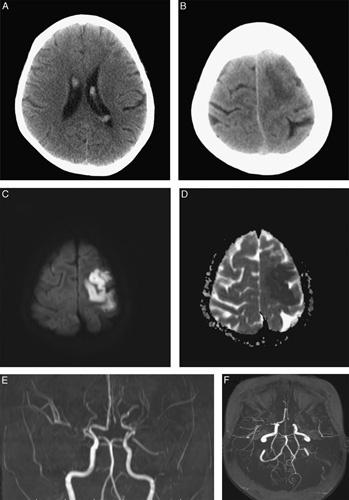

Here we report a case of Moyamoya syndrome associated with Graves' disease in a 19-year-old girl with sudden weakness of the right arm, progressive caries, and alopecia for 4 years. Brain magnetic resonance imaging revealed acute intraventricular hemorrhage and cerebral infarction of left middle cerebral artery territory and narrowing of the proximal portion of bilateral anterior and middle cerebral arteries.

我们在此报告一例 19 岁女性患者,因右侧手臂突然无力、渐进性龋齿和脱发 4 年就诊,诊断为格雷夫斯病合并烟雾病。颅脑磁共振成像显示左侧大脑中动脉区域急性脑室出血和脑梗死,双侧大脑前动脉和大脑中动脉近端狭窄。